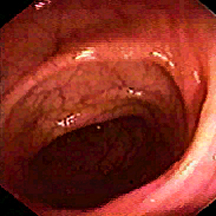

• Endoscopic appearance of the normal sigmoid colonic mucosa. The fine vasculature is easily visible and the surface is shiny and smooth. The folds are of normal thickness: here

Colonoscopy — The majority of colon and rectal cancers are endoluminal adenocarcinomas that arise from the mucosa. Colonoscopy is the single best diagnostic test in symptomatic individuals, since it can localize lesions throughout the large bowel, biopsy mass lesions, detect synchronous neoplasms, and remove polyps, The air contrast barium enema, supplemented with flexible sigmoidoscopy, is also used, but the diagnostic yield of this combination is less than that of colonoscopy for the evaluation of lower tract symptoms